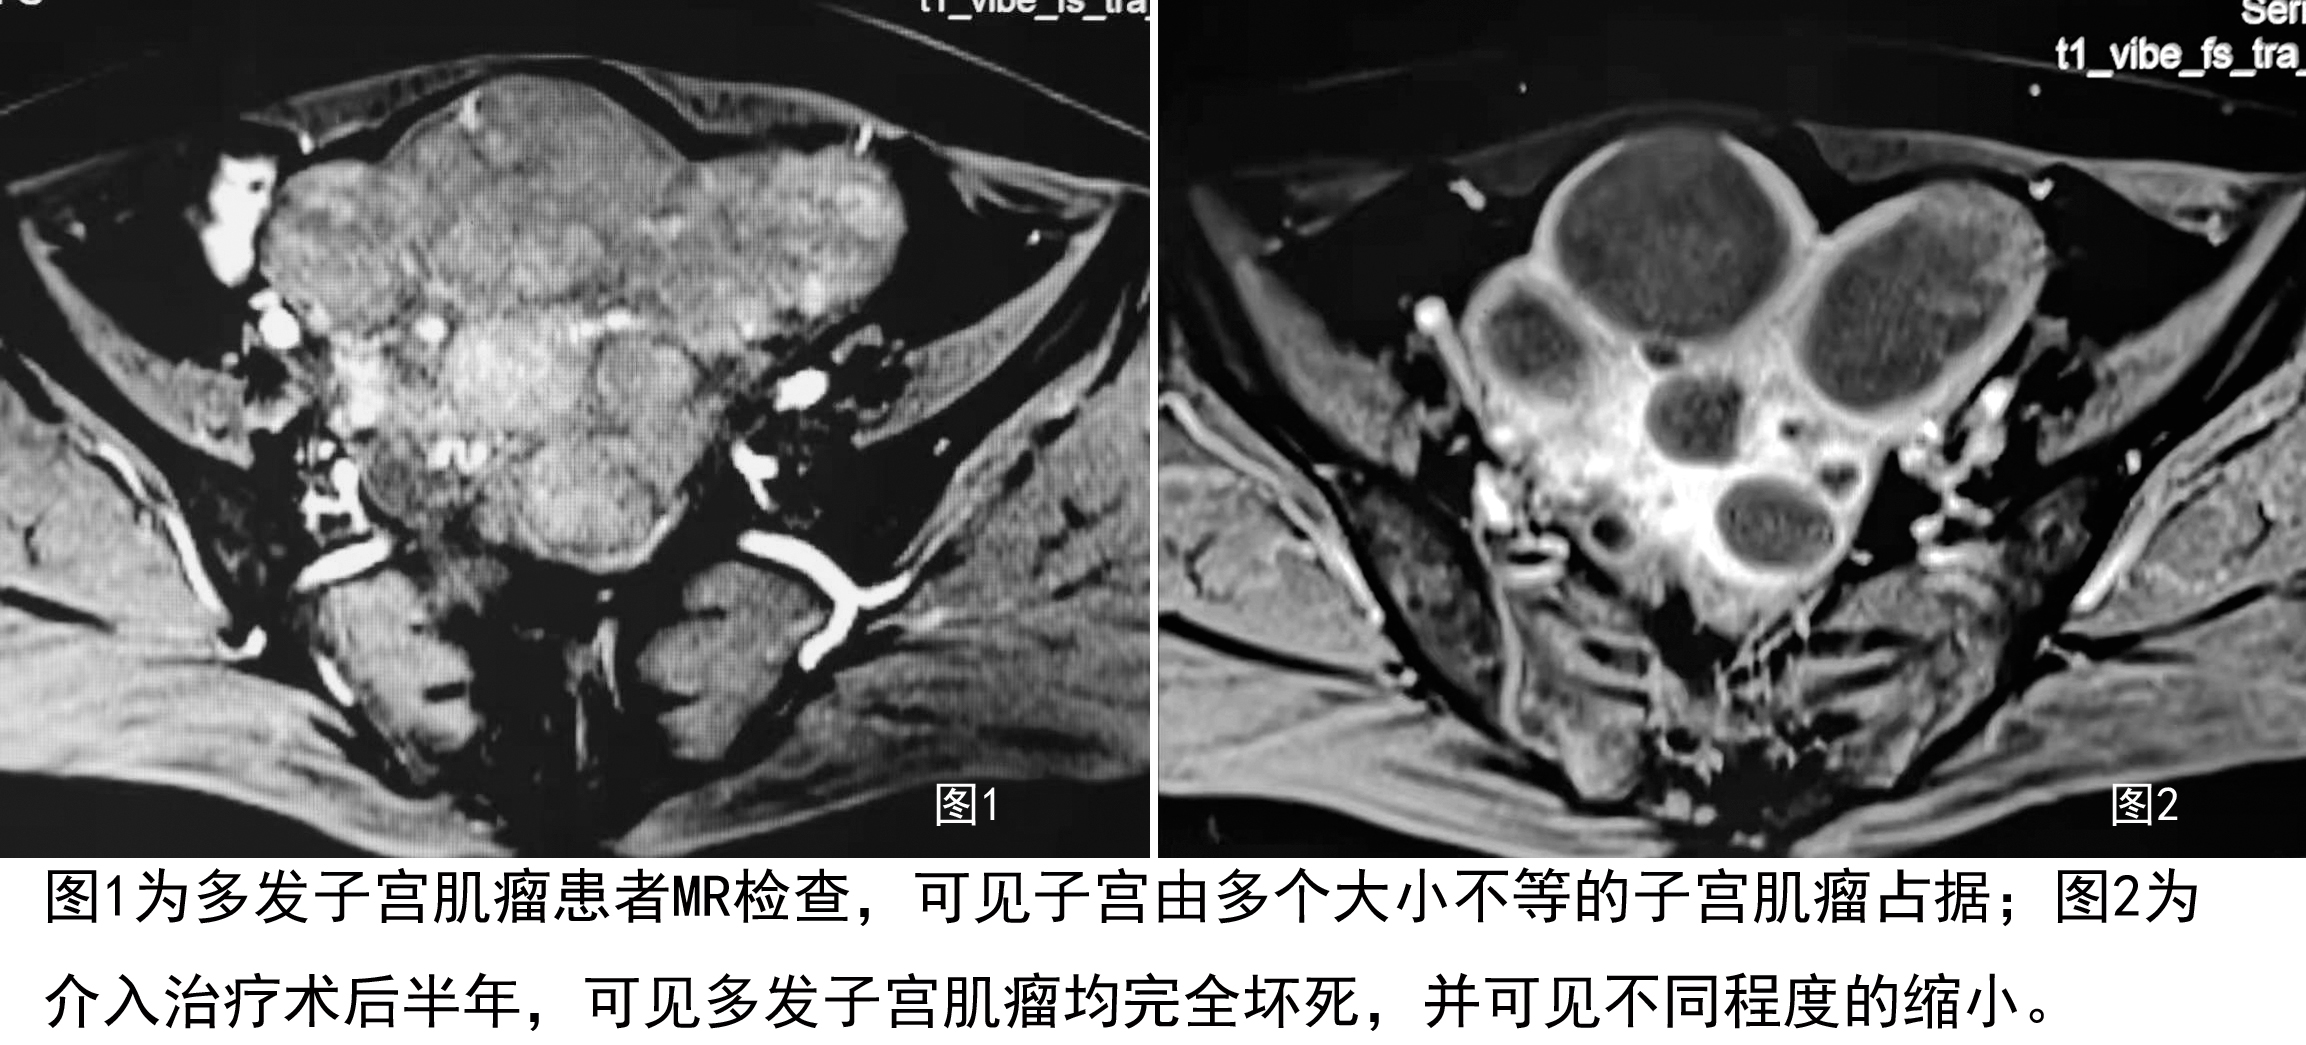

3. 对多发性肌瘤的治疗效果更好:子宫肌瘤患者有很多一部分比例为多发肌瘤患者,部分患者的肌瘤可多达数个甚至数十个,这种患者若不切除子宫,手术治疗后往往在短期内复发。介入治疗则不然,无论肌瘤有多少,只要导管插管到位,对子宫肌瘤供血动脉进行安全彻底的栓塞,术后所有肌瘤都有效,复发率较小。因此介入治疗对多发性子宫肌瘤患者有更大的优势。